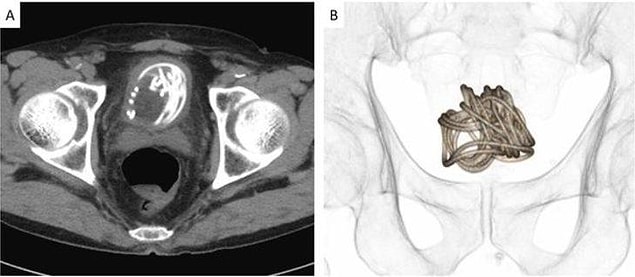

Ağrısı olduğu için Dokkyo Üniversitesi Tıp Fakültesi’ne giden 79 yaşındaki adamın penisinden 2 metrelik atlama ipi çıktı.

Uzmanlar, idrar yapma konusunda zorluk yaşadıktan sonra röntgeni çekilen adamla ilgili daha evvel bu türlü bir görmediklerini lisana getirdi.

Profesör Toshiki Kijima, ipin uzunluğu ve mesaneye dolanması düşünüldüğünde transüretral ekstraksiyon sıkıntı olduğunu belirtti.

Mesaneye yerleşen ip, mesane kasıldıkça kıvrıldığı için ameliyatla karnından çıkarıldı.